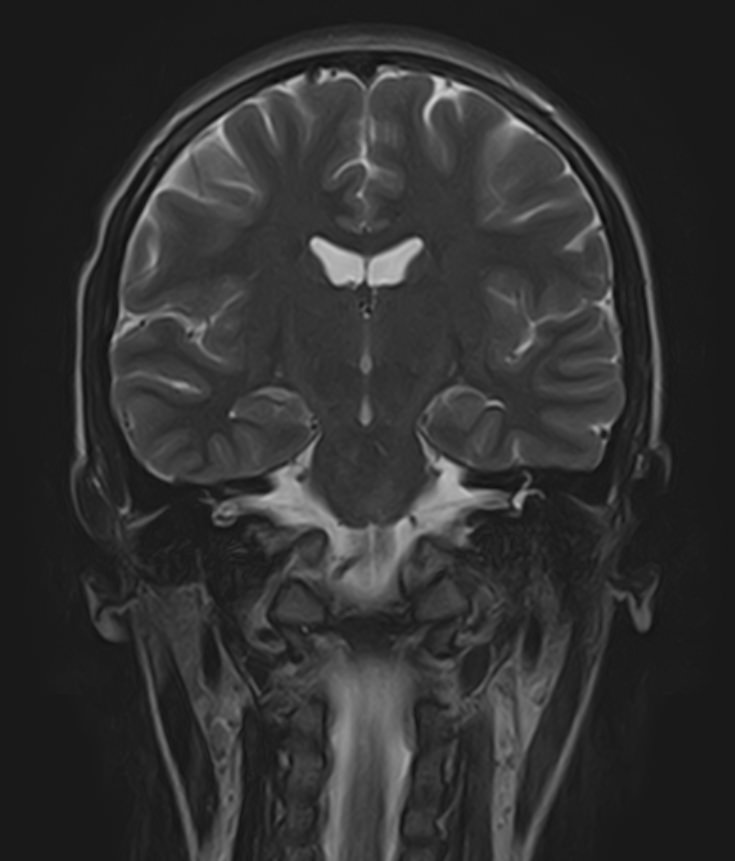

В нашей клинике мы проводим комплексное исследование, включающее МРТ головного мозга и всех отделов позвоночника. Методика комплексного обследования применяется при наличии у пациента сочетанных поражений головного мозга, спинного мозга и позвоночного столба.

Стандартная МРТ головного мозга дает важную информацию о состоянии и структуре мозговой ткани для выявления большого числа заболеваний, в том числе опухолевых образований, демиелинизирующих заболеваний, воспалительных процессов головного мозга и мозговых оболочек.

При подозрении на распространенный процесс с поражением различных уровней позвоночника целесообразно проведение МРТ для диагностики дегенеративно-дистрофических заболеваний, травматических, воспалительных изменений, а также опухолевых процессов позвоночника. Метод позволяет оценить состояние структур позвонков, позвоночного канала с расположенным в нем спинным мозгом и окружающих мягких тканей, кроме того, является основным способом диагностики демиелинизирующих заболеваний спинного мозга.

Исследование проводится на современном томографе TOSHIBA VANTAGE TITAN 1,5 Тесла. За счет высокой индукции магнитного поля аппарат обладает  высокой разрешающей способностью, что позволяет проводить точную диагностику заболеваний центральной нервной системы и позвоночника.